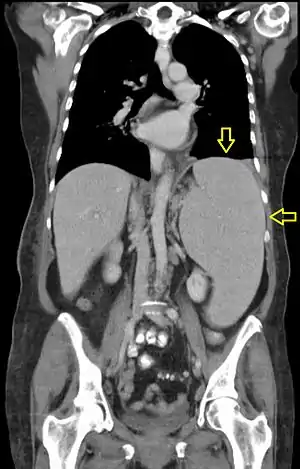

| CT scan in a patient with chronic lymphocytic leukemia, showing splenomegaly. Yellow arrows point at the spleen. | |

Abdominal CT is the most accurate and spleen need to be larger 2-3 times to be palpable below the costal margin in physical examination that can help in diagnosis.

Computed tomography shows a massively enlarged spleen ( splenomegaly).